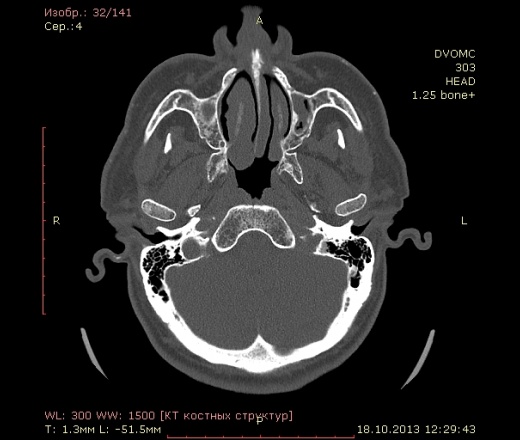

72 года. Жалобы на частые головные боли. В мозгах вроде ничего особенного, а вот пазухи...лобной нет, клиновидная недоразвитая. Вопрос вот какой:

Можно ли считать картину в, опять таки недоразвитых, верхнечелюстных пазухах (особенно слева) как хронический гайморит?(или острый такой бывает?) вся эта неоднородность и полости воздушные и мягкотканная плотность....

Написал бы как дополнение: двусторонее нарушение пневматизации в обеих в/ч, справа тотальное, слева субтотальное вспененными плотностями. Синусит? в правой в/ч возможно, полипозный (или кистознополипозный, как вам больше нравится). Рек. конс. ЛОР.